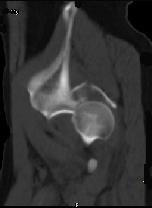

问题 男,44岁,有外伤史,请结合所提供的图像,选择最佳答案 ( )

选项 A、左髂骨骨折 B、左坐骨骨折 C、左髋关节脱位 D、左髋臼骨折并左髋关节脱位 E、左髋臼骨折

答案 D